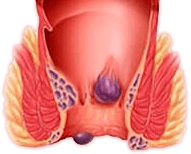

La cosa principale del problema delle emorroidi è che in nessun

caso dovrebbe essere trascurato. Non appena compaiono i primi

sintomi, è necessario iniziare a combattere il problema. Lo

stile di vita e la nutrizione sono importanti, ma se i sintomi

delle emorroidi sono già comparsi, solo queste misure non

aiuteranno. Se non ti accorgi in tempo, purtroppo, solo la